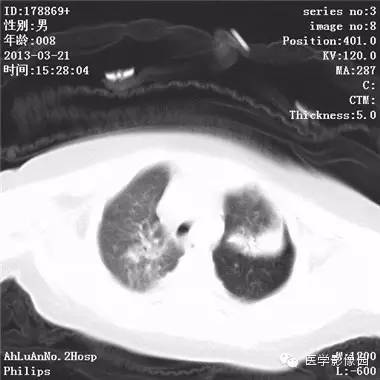

【病例】支气管异物1例CT影像表现

患儿男,8个月,呛咳,发热一周。实验室检查白细胞及中性粒细胞增高。

两肺肺纹理增多、增粗,右肺可见斑片状、片絮状模糊影,边界欠清;左肺上叶见楔形高密度影,内可见支气管征,尖端指向肺门;左肺下叶肺野透亮度增强;另见左肺主支气管内可见块状软组织密度影。

支气管异物(花生米)伴两肺炎症(追问病史,患儿奶奶层于一周前喂食患儿花生米,当时疑似“呛进去”,后来见好了也就没留意)。